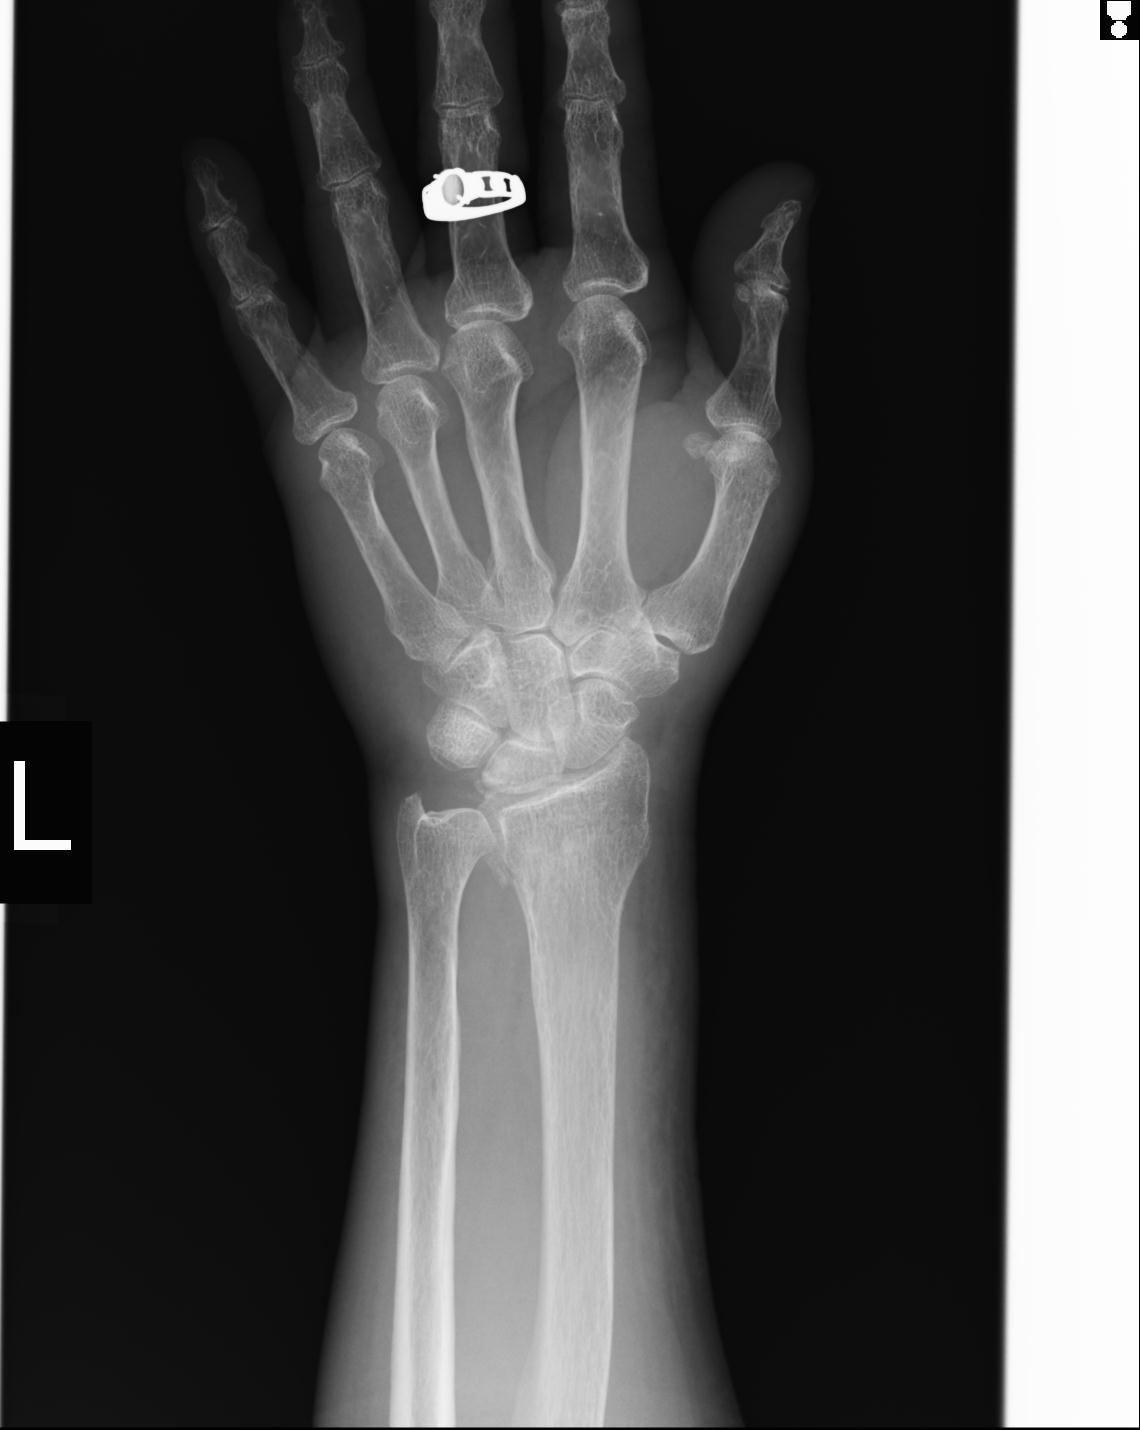

46666 1/23 両股正面+軸と右手関節 2R 76歳女性 右橈骨遠位端

46666 1/28 両股正面+軸と 1/26 右手関節 2R 76歳女性 右転子部骨折